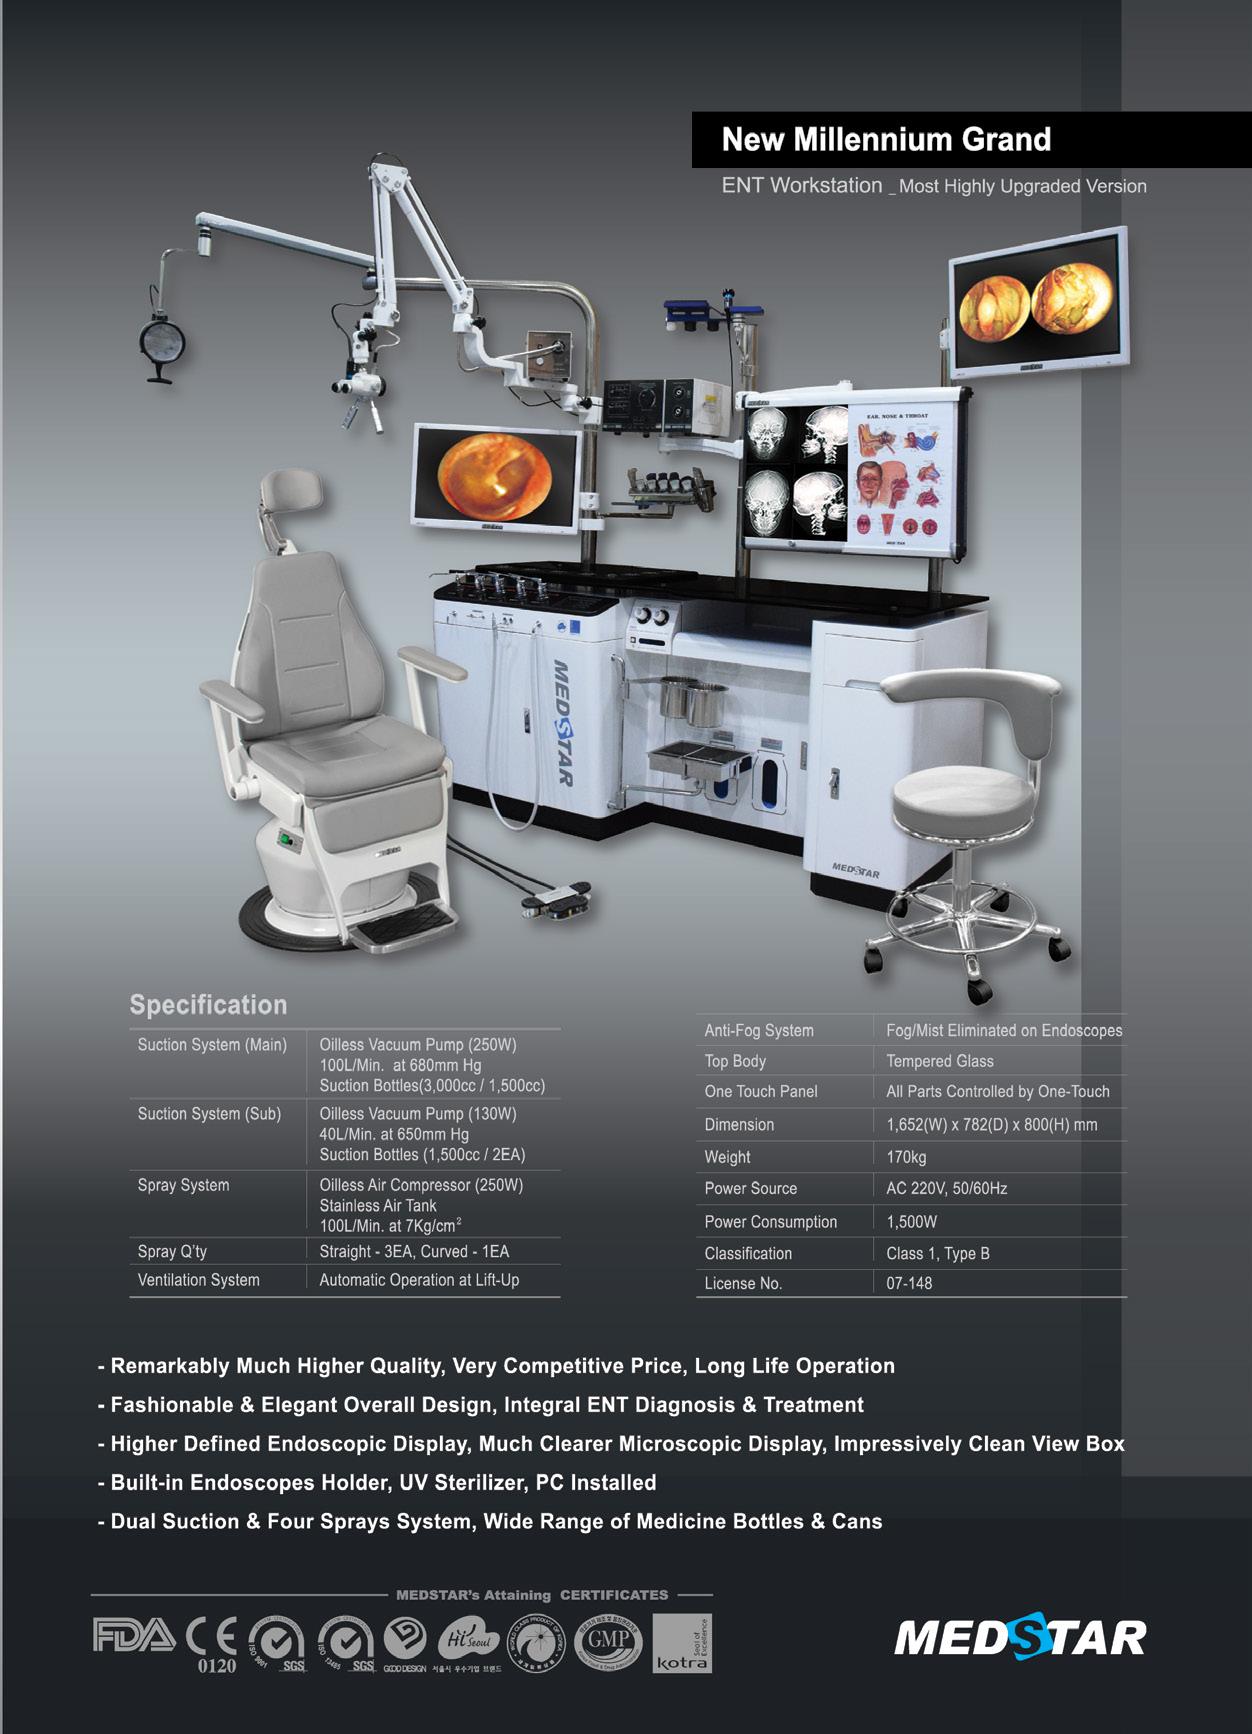

Copii între 3 luni-10 ani: o presare de picurător ( 7-8 picături) dimineața înainte de masă și seara înainte de culcare sau 15 picături în priză unică pe zi; se pot administra sublingual sau la copii mici ori necooperanți în timpul somnului în șanțul gingivo-labial >10 ani, adulți, seniori: 2 presări de picurător (15 picături) administrate sublingual, dimineața înainte de masă și seara înainte de culcare. Picăturile se mențin sublingual câteva minute, pentru un contact mai bun cu mucoasa orală, apoi se înghit.

Durata tratamentului cu Lantigen B:

- la copii între 3 luni-10 ani: pentru un ciclu de tratament, se administrează 1 flacon (aproximatv 4 săptămâni), apoi pauză 2-3 săptămâni, după care se mai administrează Lantigen B încă o jumătate de flacon (2 săptămâni).

>10 ani, adulți, seniori: pentru un ciclu de tratament se administrează 2 flacoane (aproximativ 4 săptămâni), apoi pauză 2-3 săptămâni, după care se continuă administrarea a încă unui flacon (2 săptămâni)

- pentru o imunizare completă pe perioada sezonului rece, se recomandă un ciclu de administrare în septembrie, apoi pauză 2 luni, după care se continuă cu încă un ciclu de administrare în ianuarie.